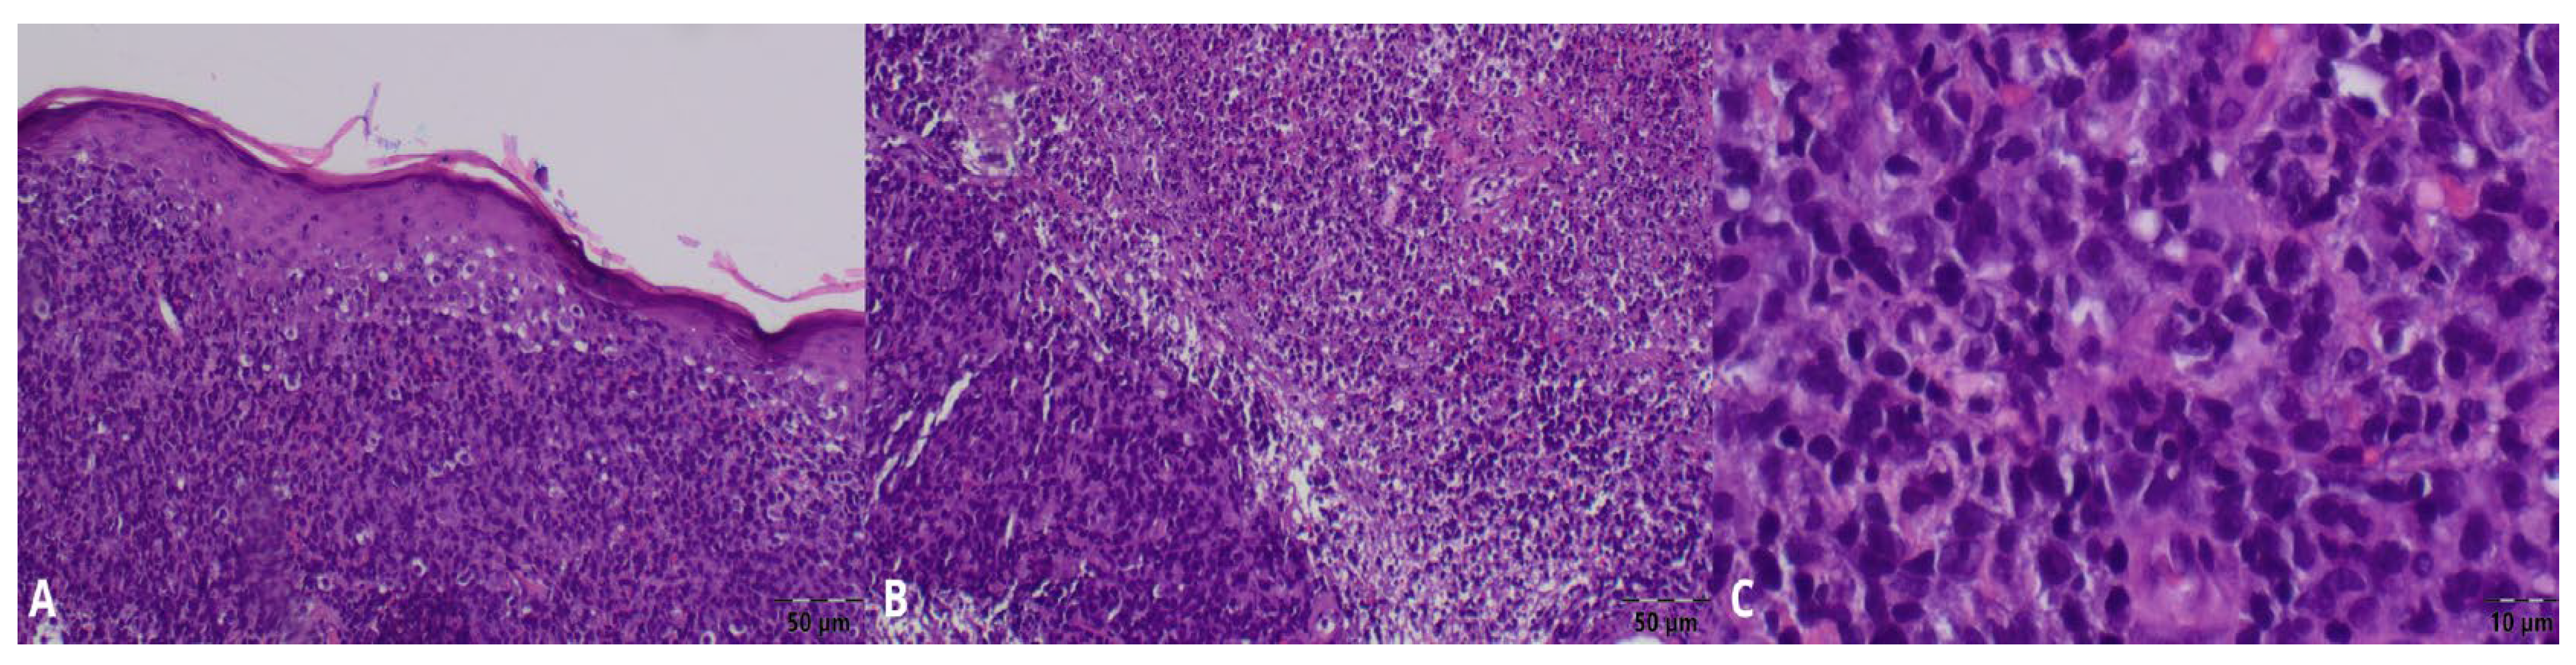

Histopathological examination of the biopsy received on June 30 revealed dense infiltration by atypical large lymphoid cells, inconsistent with PG and suggestive of a cutaneous lymphoma instead. (Figure 2A–C) Immunohistochemistry showed CD45, CD20, and CD30 positivity in the tumor cells, with CD4 and CD8 staining limited to reactive T-cells, and was negative for CK PAN. The Ki-67 proliferation index was approximately 90%. Based on these findings, the diagnosis of primary cutaneous diffuse large B-cell lymphoma, anaplastic variant (A-DLBCL), was formed. (Figure 3A–F). The rapid terminal course of the disease precluded further tests necessary for its complete staging and characterization, as well as appropriate treatment administration.

Figure 2.

Histopathological examination. (A–C) Biopsy of the lesions—diffuse infiltrate of atypical lymphoid cells filling the dermis. Numerous mitotic figures.